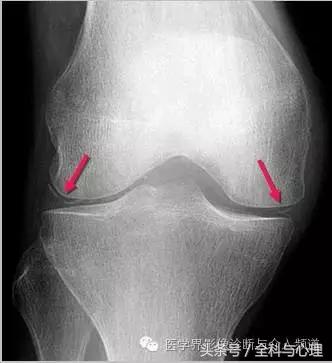

常见于膝盖、耻骨联合、臀部、尺骨三角纤维软骨复合体、肩关节。

半月板钙化